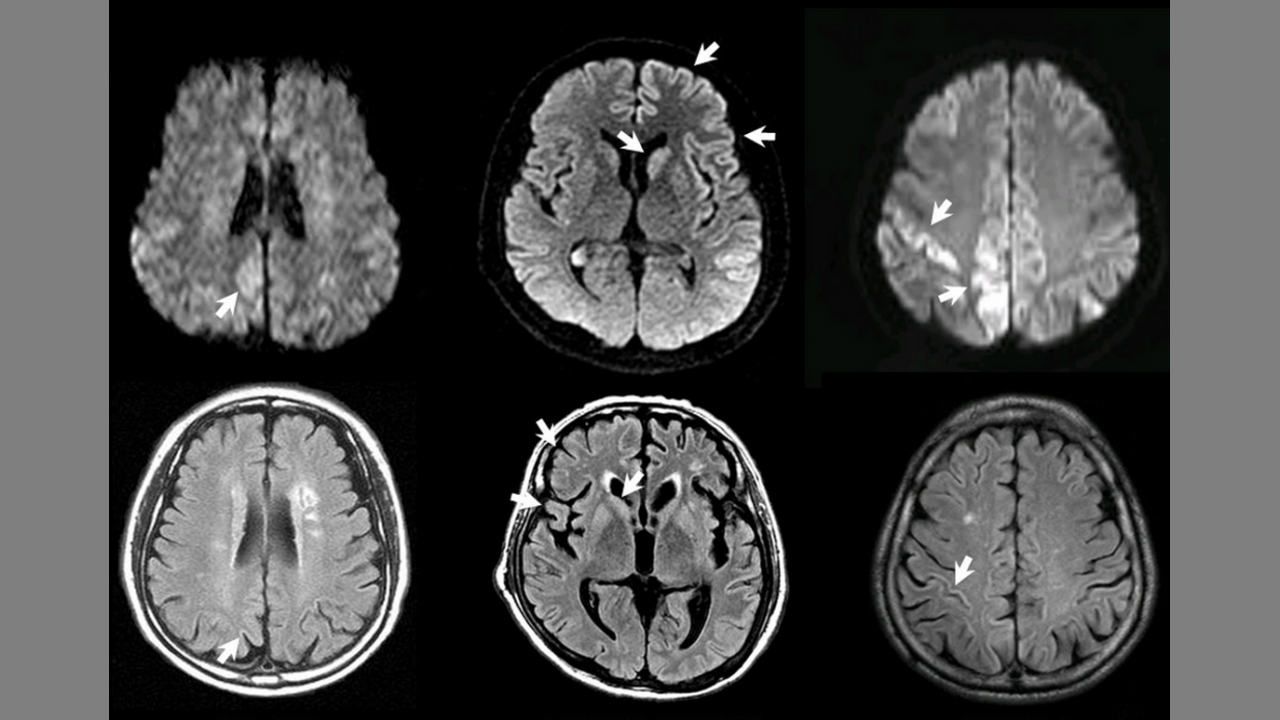

The Vaccine Will Bring On Aggressive Prion Disease